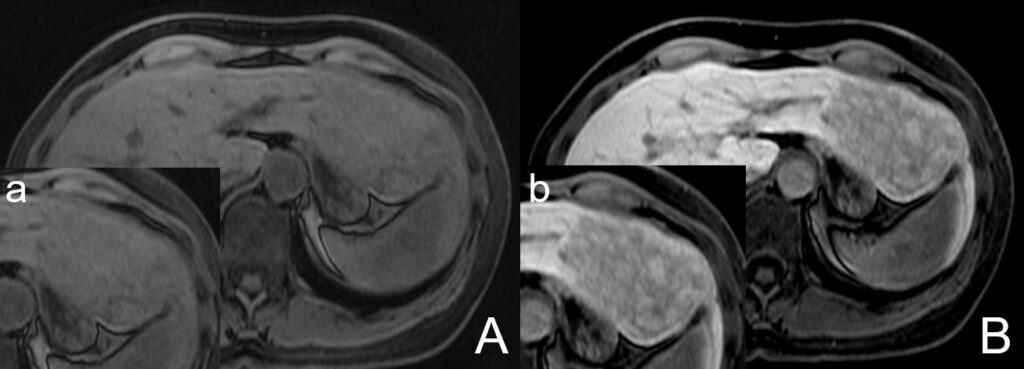

First, Reizine et al. mention that hepatobiliary phase (HPB) signal hyperintensity is not uncommon in hepatocellular adenomas (HCA), as reported in our study and several previous investigations [1-3]. We further agree that lesion hyperintensity relative to the liver and precontrast images should be interpreted with caution for the reasons given by Reizine et al. Nevertheless, we wish to emphasize that our 5-point scoring system (see our publication and Figure 1 below – (1)) rates subjective Gd-EOB uptake within the lesion itself (in steps of 25%) [1]. Lesions with a score of 0 or 1, indicating intralesional contrast uptake of up to 25%, were classified as hypointense [1]. Lesions with scores of 2-4, i.e., those with intralesional, subjective uptake of more than 25%, were deliberately defined as “significantly enhancing” or “significantly enhancing lesions” rather than hyperintense. This classification and the scoring system were refined throughout the review process of the manuscript. Figure 2 shows the precontrast and the HBP phase image of a lesion with greater than 25 percent uptake and hence rated as significantly enhancing.

Fig. 2: Example images of an IHCA showing unequivocal intralesional Gd-EOB uptake (also compared to precontrast images). Hence, this lesion was classified as a significant enhancing lesion. Compared to the liver this lesion could be interpreted as hypointense or also as iso- to hyperintense without any discriminatory power

Nevertheless, when only compared to the surrounding liver this lesion could alsobe classified as partly hypointense as well as partly iso- to hyperintense. With our scoring system though, we tried to close the gap for lesions showing a significant Gd-EOB-uptake but could be still interpreted as hypointense compared to the surrounding liver. Please note that the example lesion presented in Figure 2 is characterized by an unequivocal late-phase Gd-EOB enhancement and hence should be classified as an enhancing lesion rather than “hypointense” (if only compared to the liver). Furthermore, subjective assessment of intralesional Gd-EOB uptake in HBP should always be part of the reading process and our technique is therefore easily transferred into clinical practice also applicable to different MRI scanners (rather than quantitative assessment without validated cut-off values). Our study tries to emphasize that Gd-EOB HBP should be used as an additional feature to distinguish HCA subtypes beside the established criteria. If diagnosing HCA with Gd-EOB MRI, careful evaluation of the established criteria of each subtype has to be performed and if characteristics of IHCA or HHCA are present, subjective intralesional Gd-EOB uptake can help to strengthen the diagnosis.